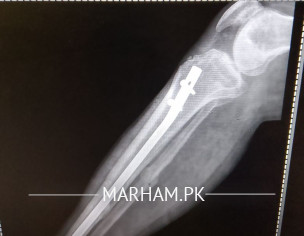

sir mane 5 month pehle opretion keya tha leg ka Lekin mere leg Mai abhi bhi pain ho Raha hai or baghir sahare k nai chal sakta sir plz check my report k Kya reason hai

seems like a case of delayed union. take vit d and calcium supplements and visit orthopaedic nearby. hopefully it will improve.

sir plz reply me k Kya Mai phir opretion karon? q k es Mai haddi ka ik piece hai jes se leg Mai soojan hothi hai or ik keel morh geya hai.plz reply me

Aap ki haddi poori tara se juri nai ay abhi jis ki waja se dard huta ay aapko koi peep waghera aati hai??

nai nai koi peep nai aati zakham belkul theek hai

sir ye haddi ka Kya karon Jo ik chota sa peace hai